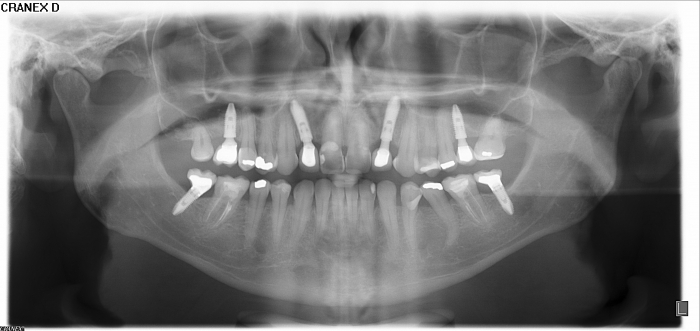

Raio X dos implantes e enxerto ósseo superior posterior

Raio X final